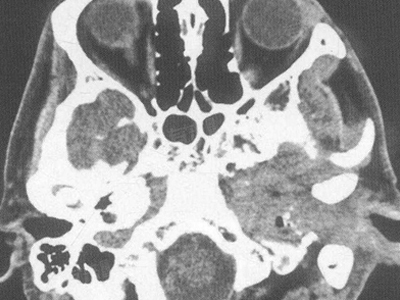

- 肿瘤:肿瘤是导致骨破坏的常见原因之一,原发性骨肿瘤,如骨肉瘤、软骨肉瘤等,可以直接破坏骨组织。转移性肿瘤,如乳腺癌、肺癌、前列腺癌等转移到骨骼,也会引起骨破坏。肿瘤细胞通过分泌各种溶解骨质的物质,如蛋白酶、细胞因子等,破坏骨的正常结构。

- 感染:细菌、真菌、病毒等病原体感染骨骼可引起骨破坏,例如骨髓炎是由细菌感染引起的骨炎症,可导致骨组织的破坏和坏死。结核分枝杆菌感染也可引起骨结核,造成骨破坏。感染性骨破坏通常伴有局部疼痛、红肿、发热等症状。